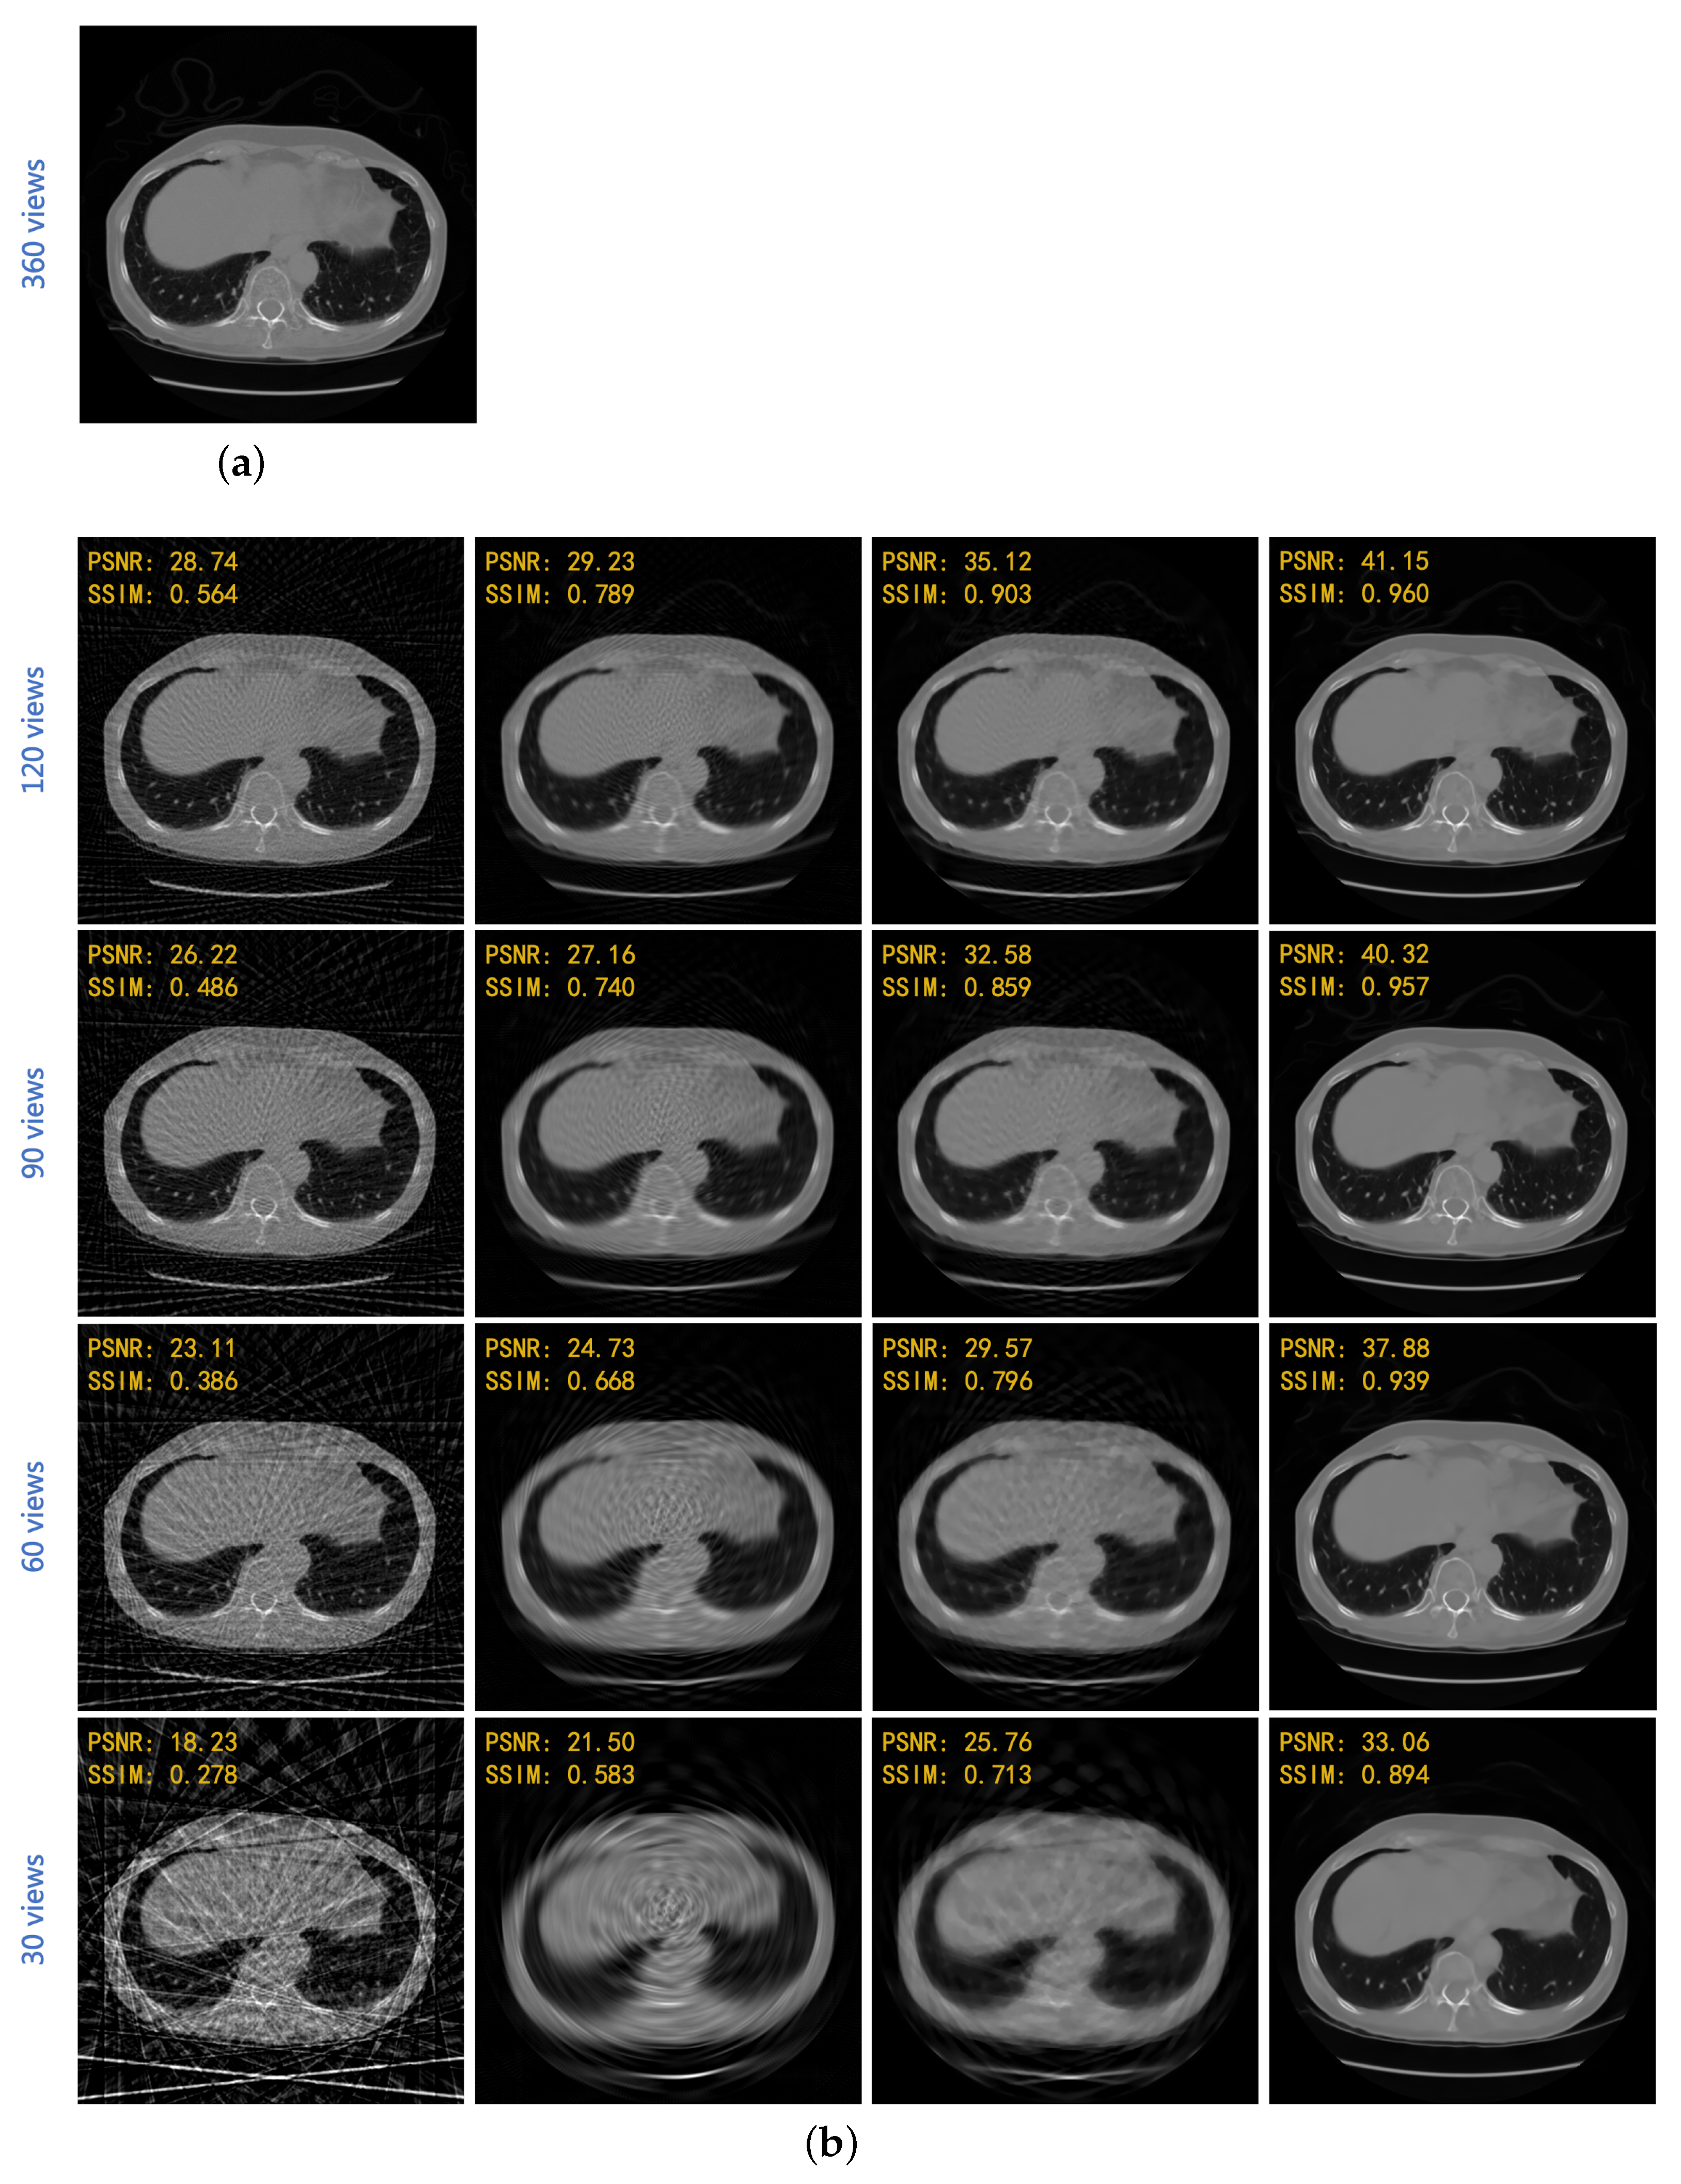

| FBP | Linear + FBP | SART-TV | Proposed | |

|---|---|---|---|---|

| 120 views | 28.725 | 30.241 | 34.405 | 41.049 |

| (3-degree) | 0.558 | 0.802 | 0.903 | 0.958 |

| 90 views | 26.702 | 28.475 | 32.190 | 40.204 |

| (4-degree) | 0.483 | 0.765 | 0.862 | 0.956 |

| 60 views | 23.259 | 26.279 | 30.085 | 37.718 |

| (6-degree) | 0.391 | 0.698 | 0.810 | 0.938 |

| 30 views | 19.496 | 23.399 | 26.711 | 33.100 |

| (12-degree) | 0.280 | 0.624 | 0.726 | 0.891 |